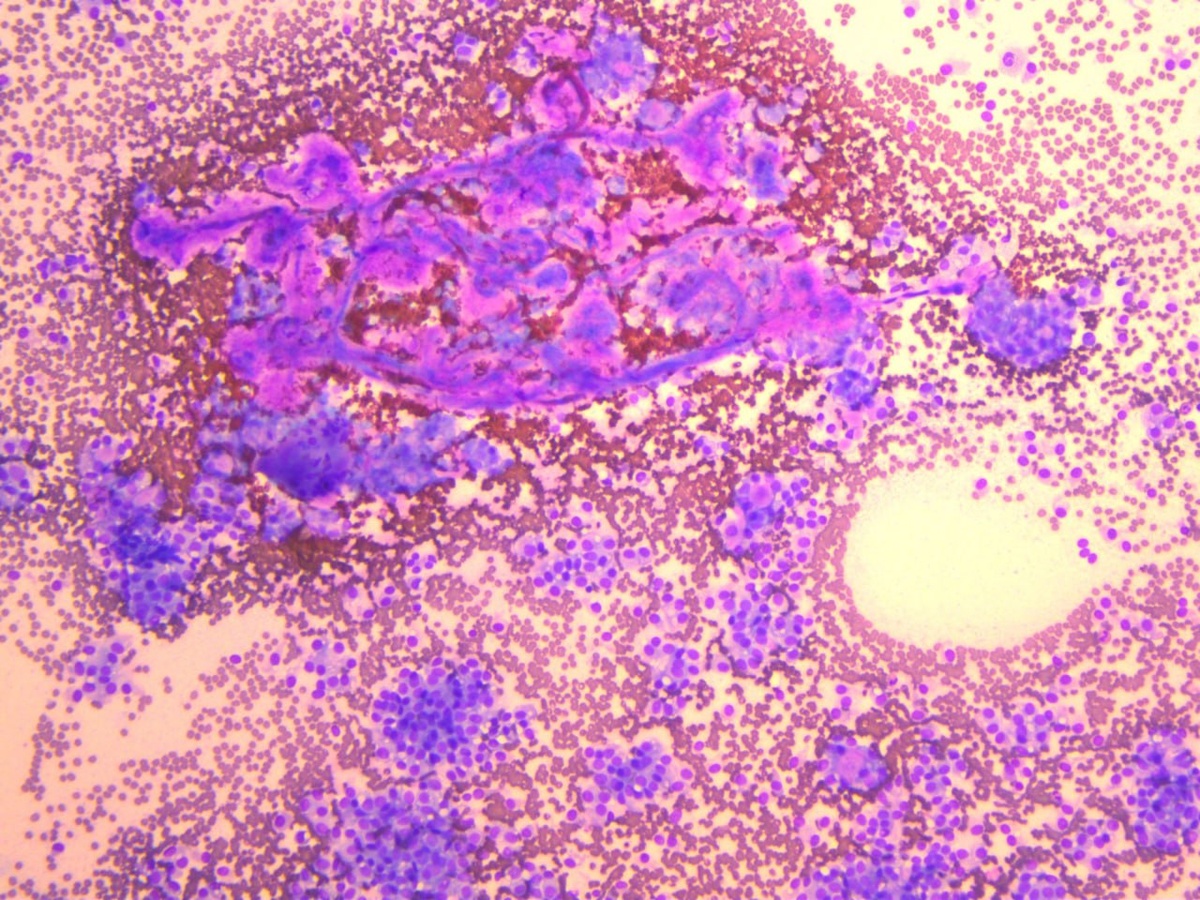

В препарате ТИАБ поджелудочной железы (5 стекол) многослойные папиллярные клеточные структуры на фиброваскулярной основе, группы из клеток поджелудочной железы с признаками структурной и архитектурной атипии, фрагментарно расположенный муцин, эритроциты. Цитологическая картина соответствует диагностической категории ЗЛОКАЧЕСТВЕННЫЙ ПРОЦЕСС (VII), учитывая цитологические паттерны, солидная псевдопапиллярная опухоль. (World Health Organization Reporting System for Pancreaticobiliary Cytopathology/WHORSPC, 2023) #цитология #поджелудочнаяжелеза #жкт